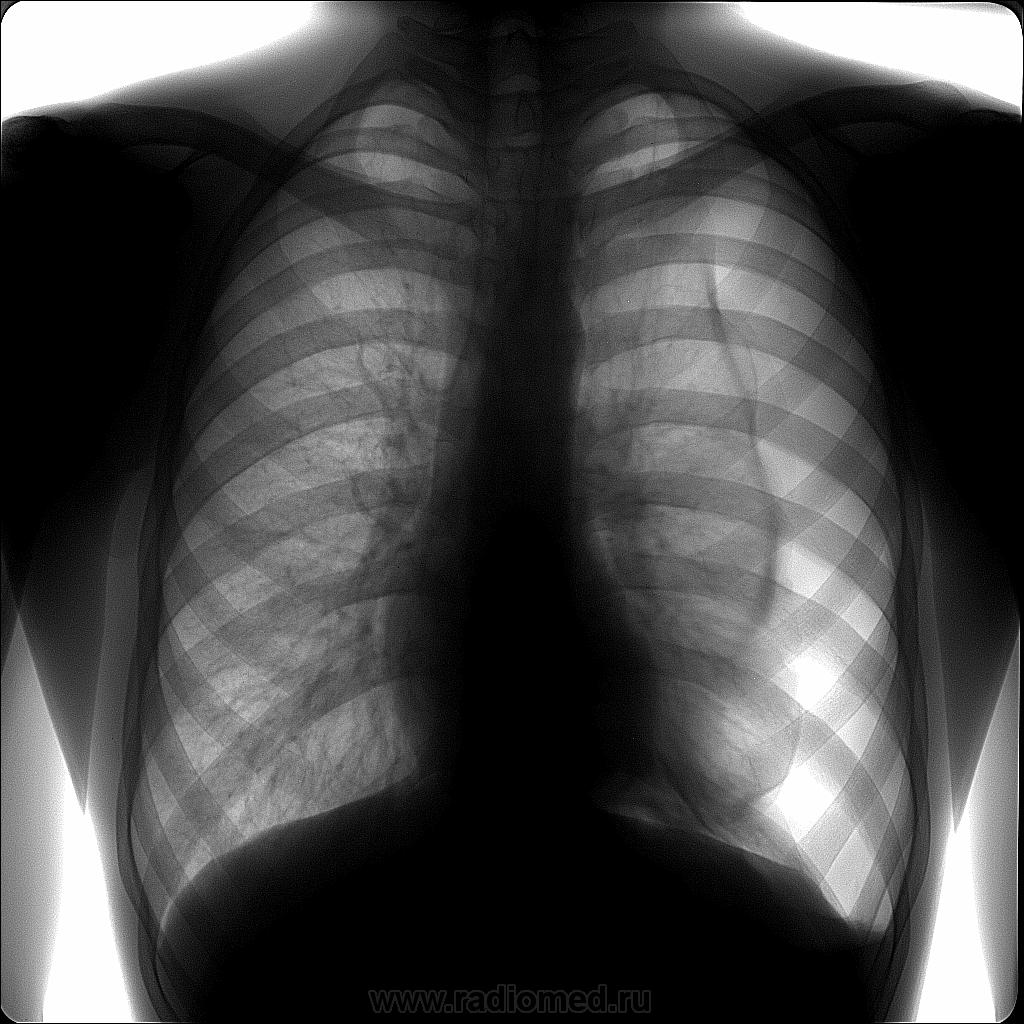

Молодой человек прошел профилактическую флюорографию. Жалоб нет. Не состоял, не болел, не лечился. Припомнил, что две недели назад подскользнулся и упал на пятую точку.

Спонтан спонтаном а в синусе что выпот или плевральные? А спонтан красивый.

Все не так:жалоб нет,а должны,в синусе жидкость,а переломов ребер не видно,легкое полностью не спалось,почему?что то мешает?Может булла лопнула от падения?всетаки что то в этом легком есть.А после расправления легкого снимки будут?

Легкое полностью спадаться и не обязано. А выпот, по идее, должен быть с горизонтальным уровнем.

Легкое не всегда спадается полностью, все зависит от причины, состояния легкого, наличия спаек и т.д. После расправления легкого снимки обязательны, хотя бы в качестве контроля. Но это сделают в стационаре, я, конечно, поинтересуюсь.

Было бы очень интересно.Но нас учили,что если легкое полностью не спадается.значит оно порочно,причины разные,даже если просто фиброзные изменения.

О причинах пневмоторакса - как правило - буллезные изменения...Для примера - вчерашня рентгеноскопия...прицельные снимки...да две картинки из интернета...